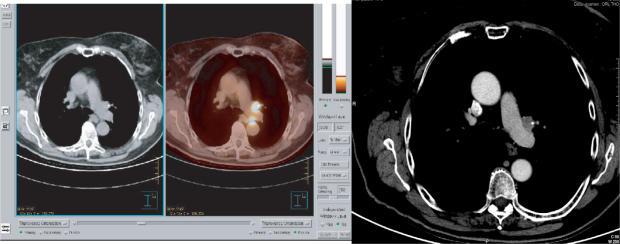

Positron emission tomography (PET)/computed tomography (CT) imaging is frequently requested in Oncology. Radiologists and nuclear medicine physicians are often asked to perform a panel of imaging examinations as part of the initial staging or follow-up of cancer patients. Medical imaging must therefore integrate polyvalent skills enabling imaging specialists to understand and interpret all types of images. In this context, PET imaging combined with non-enhanced CT, and diagnostic quality contrast-enhanced CT scan and optimisation of CT settings, is part of this multidisciplinary approach requiring the specific skills of a radiologist and a nuclear medicine physician. This approach must therefore be conducted in both directions: radiologists and nuclear medicine physicians should both know how to correlate PET and CT images, while preserving the specificities of each discipline. Radiologists need to be aware of several aspects of PET imaging: PET technology, the examination procedure and injection of iodinated contrast agent for high quality diagnostic CT, ideally followed by double interpretation of CT images, PET images and fused images. Radiologists should be familiar with PET imaging, as this procedure may be associated with several pitfalls and artefacts that need interpretation by a trained specialist. The authors analyse the examination technique of PET combined with non-enhanced and/or contrast-enhanced CT and the proposals for optimal interpretation of normal or pathological PET/CT fusion images.

肿瘤学领域经常需要进行正电子发射断层扫描(PET)/计算机断层扫描(CT)成像。放射科医生和核医学医生经常被要求进行一系列成像检查,作为癌症患者初始分期或随访的一部分。因此,医学成像必须整合多种技能,使成像专家能够理解和解读所有类型的图像。在这种情况下,PET成像与非增强CT相结合,以及具有诊断质量的增强CT扫描和CT设置的优化,是这种多学科方法的一部分,需要放射科医生和核医学医生具备特定技能。因此,这种方法必须双向进行:放射科医生和核医学医生都应该知道如何关联PET和CT图像,同时保留各学科的特殊性。放射科医生需要了解PET成像的几个方面:PET技术、检查程序以及为高质量诊断CT注射碘化造影剂,理想情况下随后对CT图像、PET图像和融合图像进行双重解读。放射科医生应该熟悉PET成像,因为这个过程可能会出现一些需要经过培训的专家进行解读的陷阱和伪影。作者分析了PET与非增强和/或增强CT相结合的检查技术,以及对正常或病理PET/CT融合图像进行最佳解读的建议。